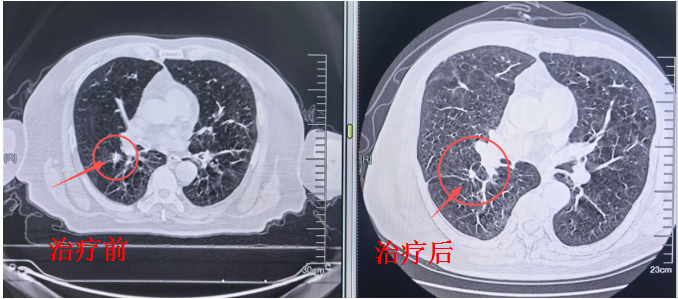

1. 肺部病灶:射波刀——精确护肺,无创治瘤

针对肺部病灶,团队接纳了射波刀。这是一种无创诊治工夫,无需开刀、无需麻醉,对脆弱肺功能影响极小。更弥留的是,射波刀具备毫米级精确度,可收尾多角度、动态跟踪照耀,在澈底糟塌肿瘤的同期,最大终结保护周围平日肺组织。

诊治周期短、创伤小、规复快,为无法手术的肺功能受损患者开辟了新旅途。

肺部复查